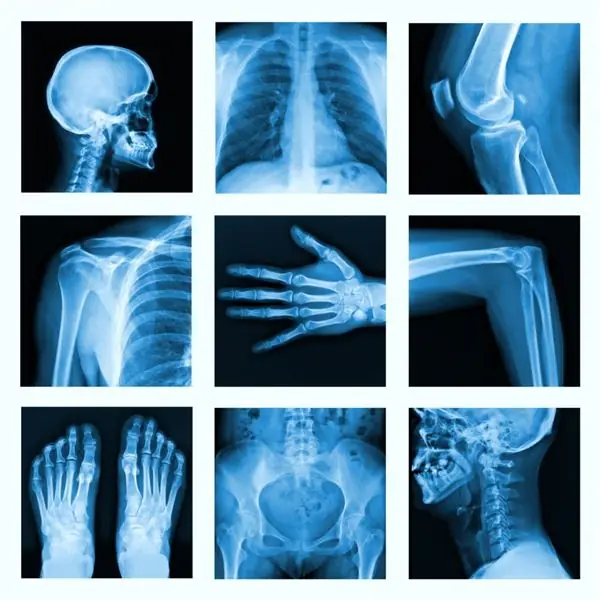

Коллаж из многих рентгеновских снимков в очень хорошем качестве

Дегенеративные заболевания часто поражают костную систему.